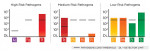

Upon the discovery of inflammation represented by bleeding, the office initiated a salivary diagnostic test from OralDNA, shown in Figure 2. Clearly, the test showed the presence of pathogenic bacteria with a large pathogen load. Four quadrants of SRP were recommended in a conventional manner using a combination of ultrasonic and hand scaling plus chlorhexidine as an irrigant. No other treatment modalities were used.

At the 7-week disease reevaluation, periodontal charting showed improvement in pocket depths and reduction in bleeding sites to five. Another test using MyPerioPath® was administered. The results after conventional SRP produced improvement in bleeding and pocket depth but affected the pathogen profile very little (Figure 3). This provoked the need to take a more comprehensive approach to disease treatment and employ a total-mouth disinfection methodology. This method addresses the following areas:

After developing a method to be much more comprehensive (ie, a total mouth disinfection approach), treatment following the above protocol was reinitiated. The patient was kept on a tight 2-month re-evaluation schedule until zero bleeding was established. The patient was then retested using MyPerioPath® (Figure 4). With the use of a total-mouth disinfection approach, the microbial profile was altered through eradication, suppression, or alteration of the bacterial load. It is important to note this profile was measured when there was zero bleeding, suggesting gingival stability.